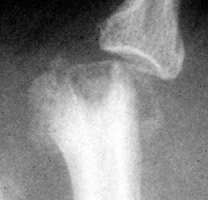

Gout Gout: Large erosion with overhanging edges 1st metatarsal

++